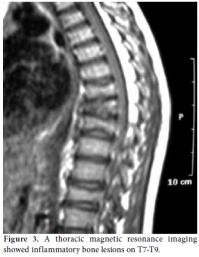

A 10-year-old boy was referred to the Pediatric Rheumatology Unit at the University Hospital Federal University of Pernambuco, Recife in 2008 with a fiveyear history of intermittent pain in his left clavicle, right hip, ankles, and dorsal spine. In 2006, he was admitted to the Pediatric Unit complaining of back pain, fever, and a mass over his left clavicle. Blood tests showed a C-reactive protein (CRP) level of 24 mg/dl and an erythrocyte sedimentation rate (ESR) of 39 mm/h. A chest X-ray confirmed the mass over his left clavicle (Figure 1). Septic osteomyelitis was diagnosed, although his blood and bone cultures were negative. A course of an empirical antibiotic (cephalothin) and NSAIDs was prescribed. He was later referred (after one year) to the Orthopedic Unit where a thoracic computed tomography (CT) scan showed the volume of the left clavicle had increased due to an area of hyperostosis mixed with osteolysis. Hence, the antibiotic was changed to ciprofloxacin for three months. As there was no improvement, he was referred to the Pediatric Rheumatology Unit, where a tuberculin test and ANA were negative. A bone scan showed an increased technetium-99m (99mTc) radioisotope uptake at the left clavicle, ankle, sacroiliac joints, and T8 thoracic disc (Figure 2). Magnetic resonance imaging (MRI) demonstrated multiple inflammatory lesions between the T7 and T9 disks (Figure 3) and in the left clavicle and left ankle (Figure 4), thus confirming the findings on the bone scan and thorax CT. The results of the histological analysis of a bone biopsy were compatible with aseptic chronic osteomyelitis (Figure 5). No infection was identified by lesion or blood culture, and no malignancy was detected by imaging; hence, the possibility of CRMO was raised. An aggressive treatment with NSAIDs, alendronate 70 mg/week, methotrexate 15 mg/week, and infliximab 5 mg/kg was initiated due to the severity of the case and the delay in diagnosis. After the third infusion of infliximab, the boy became free of pain. His ESR and CRP levels were normal, and a bone scan showed a tiny uptake at the left clavicle. It should be noted that the patient and his family gave their consent for any treatment provided at the Pediatric Rheumatology Unit.

An X-ray can show areas of osteolysis at the metaphysis and diaphysis as well as the sclerosis around it.[10,11] Bone scans (99mTc), CT, and MRIs can help in the diagnosis by determining the location for a bone biopsy and assessing the activity of the disease.[11] The X-ray and MRI images were of great importance in our case since they provided evidence of the osteolysis and bone enlargement lesions.[12,13] Vertebral compression is a rare radiographic finding, but an MRI revealed compressive lesions of the spine at T7-T9 along with scoliosis in our patient. His pain was lessened after he was treated with NSAIDs.